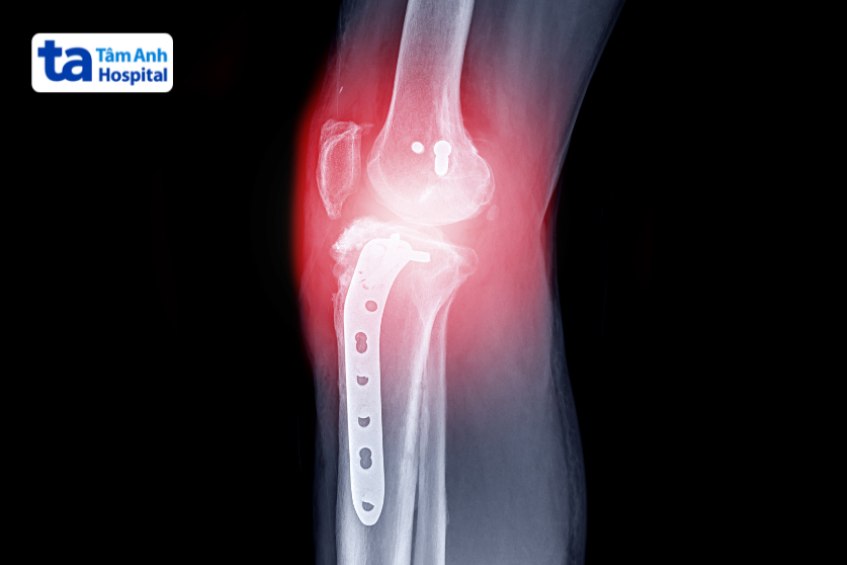

Ngược lại, trường hợp vỡ mâm chày mức độ nặng, các mảnh xương có dấu hiệu di lệch hoặc nhô ra khỏi da, nguy cơ hoại tử da… người bệnh cần phẫu thuật nhằm đảm bảo chức năng đầu gối bằng cách sắp xếp và cố định lại các phần xương bị gãy, sửa chữa dây chằng hoặc sụn chêm, thay khớp gối…